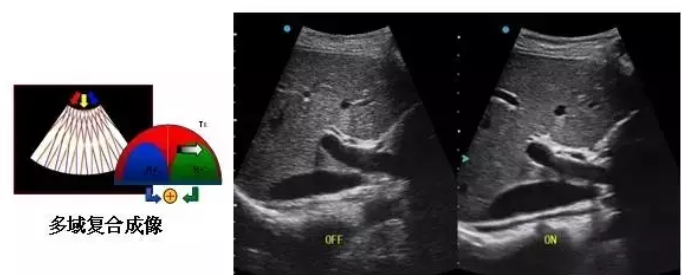

多域复合成像(XBeam):通过频率域和空间域进行复合的图像处理,能有效消除由于图像离散化和图像衰减引起的空间分辨率下降的不利影响,弥补原有图像空间分辨率的不足,获得更加清晰的图像。